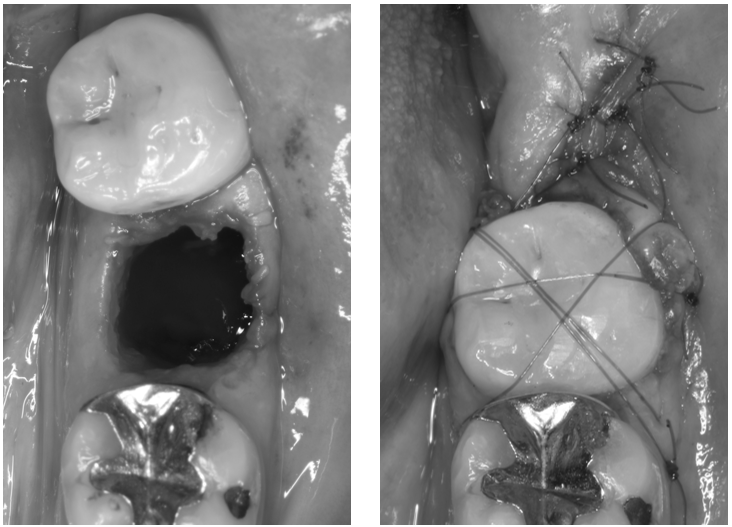

歯牙移植の症例

症例1

治療の流れ

| 患者様データ | 30代 女性 |

| 来院時の主訴 | 「左下の歯グキが腫れてきた。」 |

| 医院の診断 | 慢性根尖性歯周炎、歯根破折 |

| 通院期間 | 8か月 |

| 来院回数 | 10回 |

| 治療費 | 総額:425,000円(税抜) 【内訳】 歯牙移植150,000円、精密根管治療80,000円(大臼歯)、ファイバーポストコア20,000円×2、セラミック治療85,000円、ダイレクトボンディング70,000円 |

| リスクと副作用 | ①根管治療歯は長期的には破折するリスク ②長期的なメインテナンスが必要 ③歯根の外部吸収 |

| ここがこだわりのポイント!☝ |

術前に撮影したCT画像から3Dプリンターを用いて親知らずのレプリカを作製することで、 親知らずが乾燥することを防ぎ、成功率が上がるよう努力しています。 |